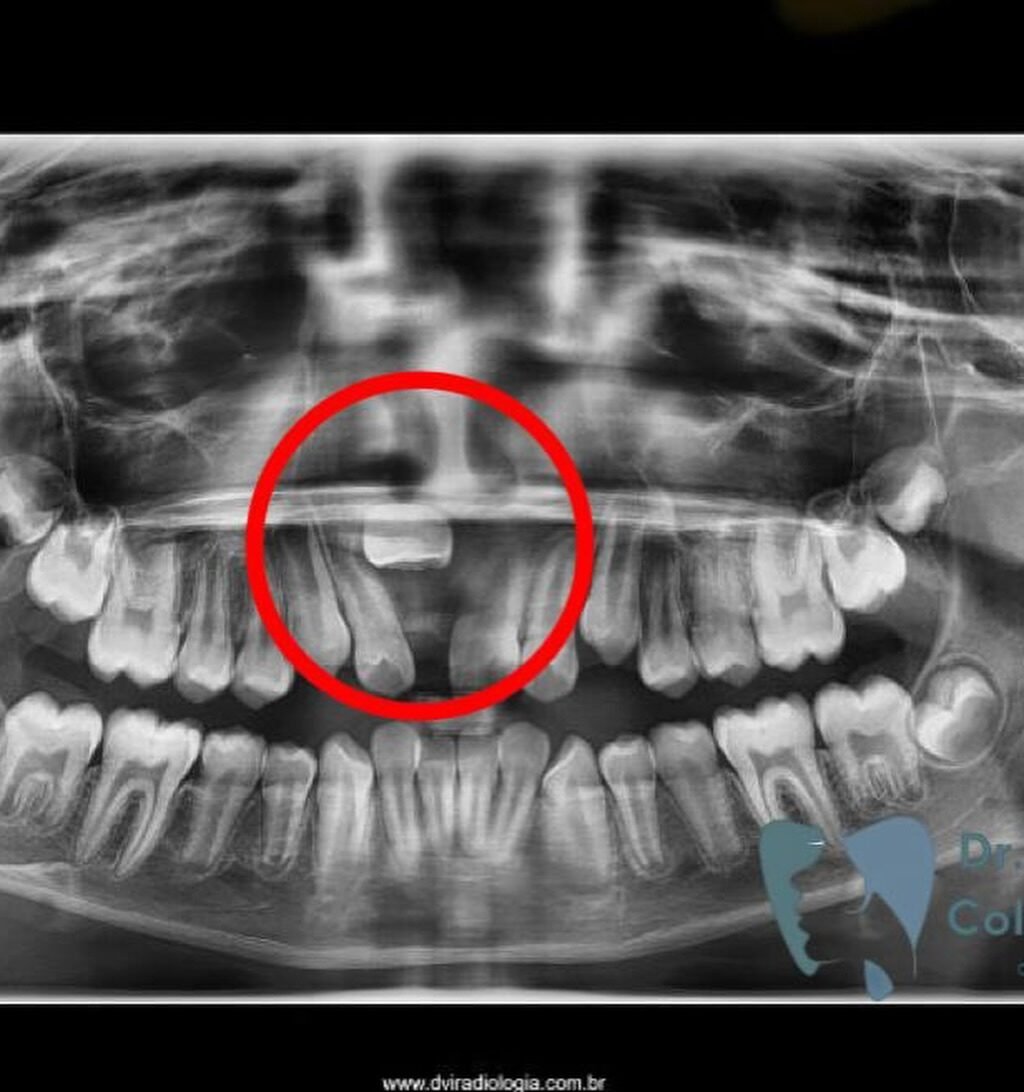

A Patologia Oral e Maxilofacial é a especialidade responsável pelo diagnóstico e tratamento de doenças que afetam a boca, mandíbula e estruturas faciais. Atua na identificação de lesões, cistos e tumores, garantindo diagnóstico preciso e tratamento adequado para preservar a saúde bucal e geral do paciente.